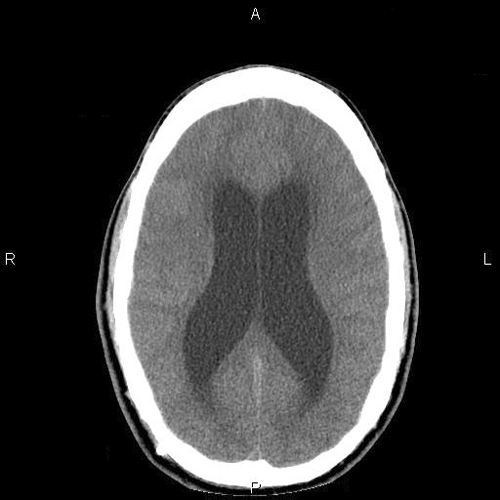

A poorly defined lesion is identified in the pineal region of the CT scan. The increased density suggest calcifications (Panel A). A moderate degree of hydrocephalus is also present (Panel B).